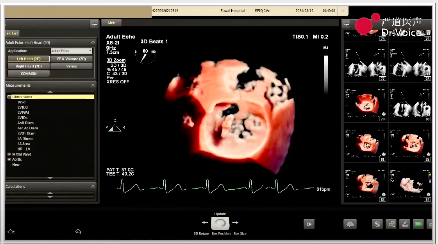

2、由于该患者病变部位为A1区及交界位置,且二尖瓣后叶较短,常规XTR型号瓣夹相对偏大,故本次手术选择NTR型号瓣夹进行夹闭合。同时,为保证前后瓣叶充分夹闭,将瓣夹靠近A1区域并适当倾斜夹闭角度。

瓣夹目标位置及夹闭角度